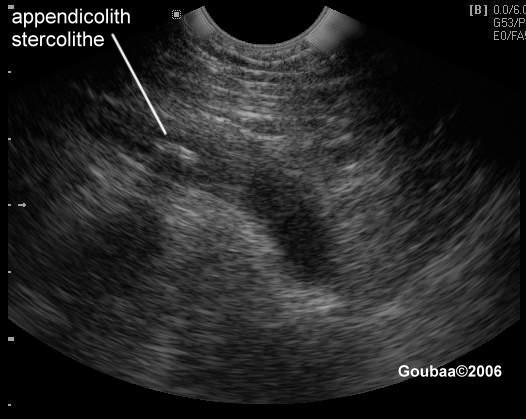

Je m'ennuyais des cliniques et des us et coutumes hospitalières alors, je me suis dit : tiens, pourquoi pas une crise d'appendicite. Oh ben oui, en voilà une idée qu'elle est bonne !

A 16H30, je me décide à aller faire une prise de sang et à 17H30 ma médecin généraliste me reçoit... pour me prendre en urgence et dernière minute un RDV pour une écho.

Car en plus, étant sous anticoagulant, je n'étais pas opérable de suite.... Il a fallu attendre le lendemain, avec un jour sans anticoagulant pour être sûr que ma coagulation rende possible mon opération.

L'appendicite !!! J'y pensais même plus à celle là, pour moi, c'était une maladie érradiquée de la surface terrestre vu que cela fait des années que je n'en ai pas entendu parler...